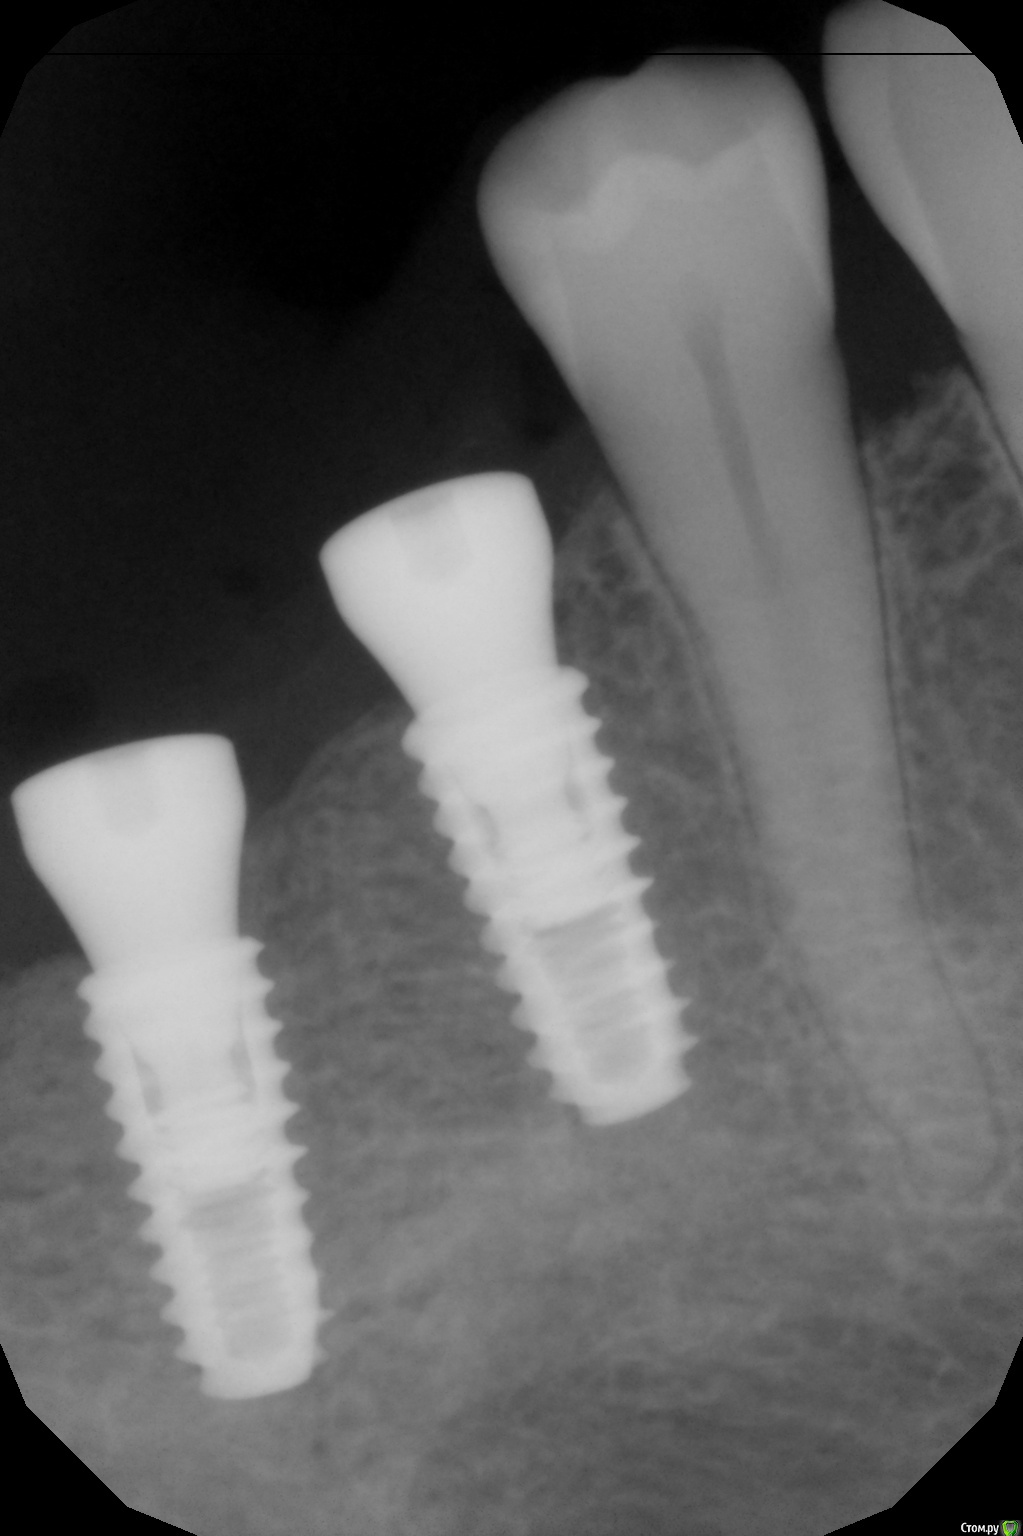

kamranchick Опубликовано 8 февраля, 2017 Автор Поделиться Опубликовано 8 февраля, 2017 А что и какой размер ставили?Послабляющий распил не делали?я тут не делал распилы, тут нет расщепления3,5-8,5 Ссылка на комментарий

kamranchick Опубликовано 8 февраля, 2017 Автор Поделиться Опубликовано 8 февраля, 2017 Спасибо за публикацию.Какова ширина гребня?5мм сверху в области кристального модуля имплантата дальше около 7мм) Ссылка на комментарий